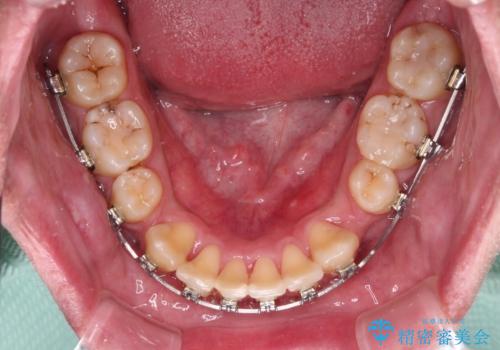

デコボコと口元の突出感を改善 抜歯矯正治療

上下左右の犬歯が八重歯になっており、口元にもやや突出感があるため、上下左右の小臼歯4本を抜歯し、ワイヤー装置にて矯正治療を行うこととしました。

右上第一小臼歯は歯根癒着により移動せず、左上第二小臼歯は移動はするものの非常に動きが鈍かったため、抜歯したスペースを閉じるまでに非常に時間がかかってしまいました。